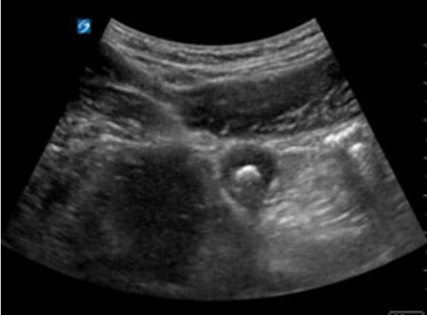

Appendicolith